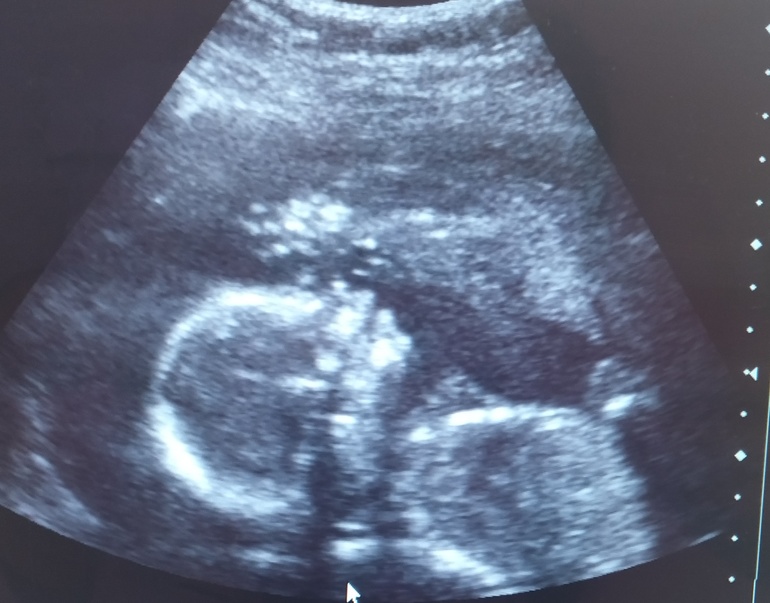

Сегодня уже 19+5, практически половина беременности - с ума сойти😯

Крошка, как и на первом УЗИ, сначала помахала ручкой, а потом отвернулась. Вреднюха, чувствую, будет, вся в мать😂

Все параметры по срокам, УЗИ хорошее;)